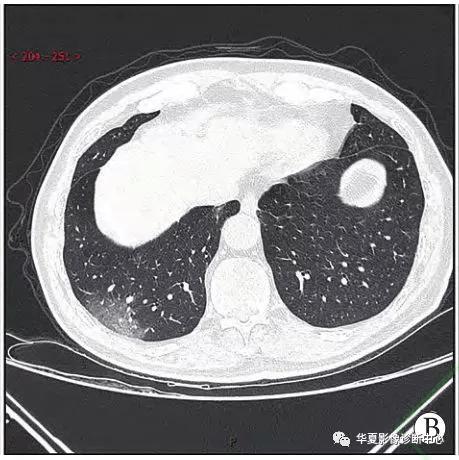

小叶性肺炎(支气管肺炎)

支气管肺炎(在支气管处有阴影,那块状影不是癌)

支气管囊肿ct表现为局部的透亮影.